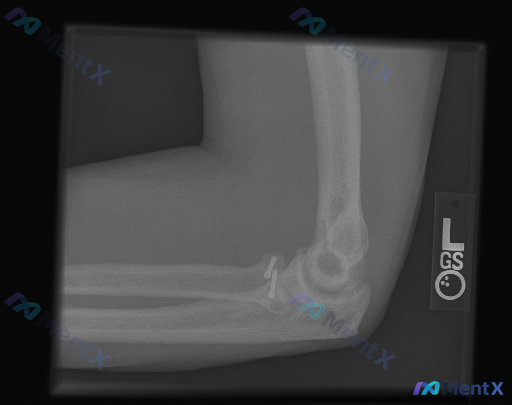

整理到一份左肘部的影像分析资料,先抛出来讨论一下。 这份是侧位X光片,基本情况是:尺骨近端有接骨板+多枚螺钉内固定,影像报了「内固定在位、骨皮质轮廓完整、关节对位好、无明显脂肪垫征」,结论倾向于「术后改变,未见明显异常」。 但结合临床背景来看,这张片子背后其实藏着几个高风险的「异常方向」——尤其是如...

整理到一张左侧肘关节侧位X光片的分析资料,先不直接说结论,大家看第一遍的时候,最突出的「与正常不同」会先注意到什么? 先提几个观察点: - 骨骼完整性/有没有异常高密度影 - 关节对位关系 - 关节周围软组织 这份资料的核心其实不只是识别异常,而是对异常性质的定性——哪些是医源性的预期改变,哪些是需...

整理到一张左侧肘关节的侧位X光片,先放核心影像所见,大家来聊聊思路: - 标注L,左侧肘关节侧位 - 肱尺、肱桡关节对位基本可,无明显脱位/半脱位 - 关键:桡骨头颈部可见高密度金属内固定物(微型螺钉类) - 前/后脂肪垫征阴性,无明显“帆船征” - 整体骨密度无弥漫异常,关节面尚平整,无明显急性骨...